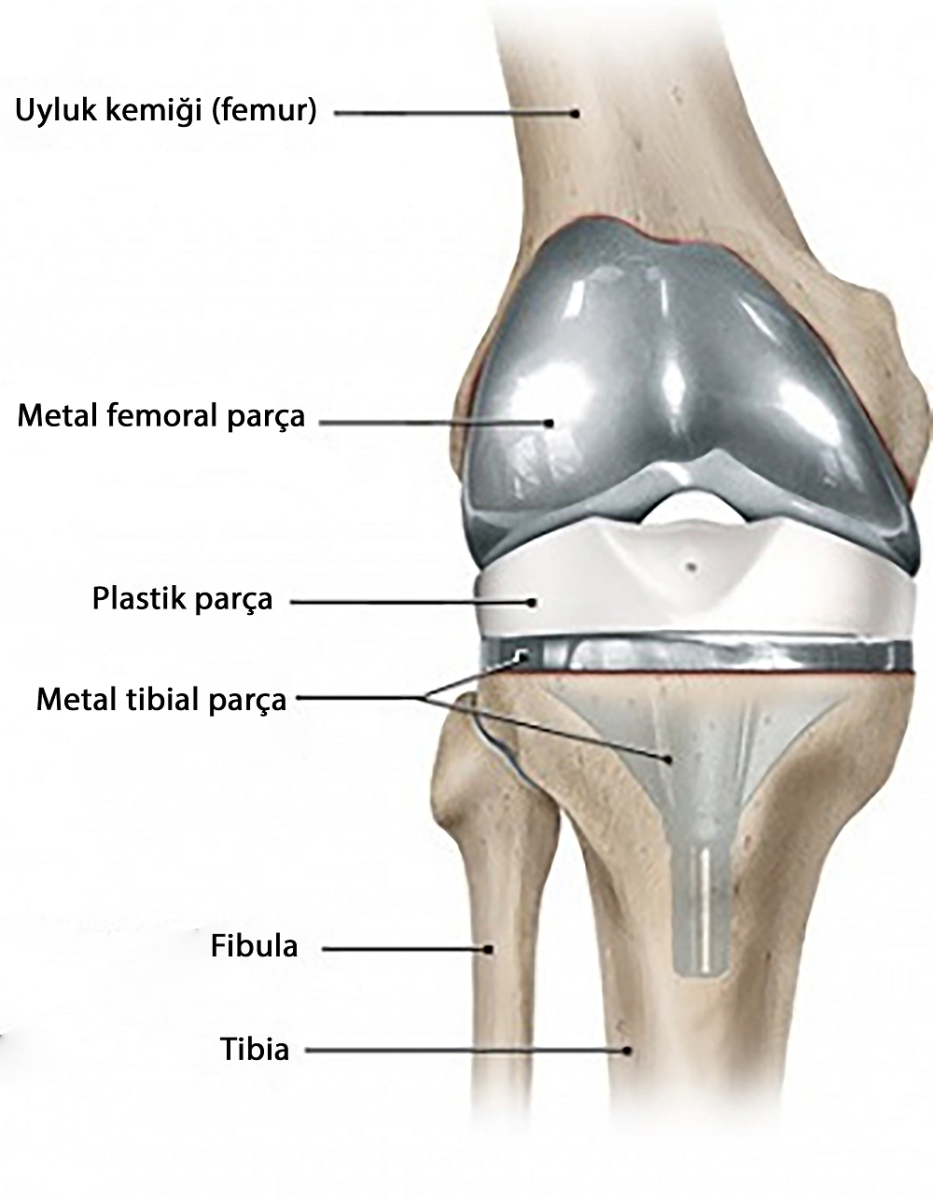

Total diz protezi aşınmış olan eklem yüzeylerinin, metal ve polietilenden imal edilen, ağrısız eklem hareketi için tasarlanmış özel parçalar ile kaplanarak yapay eklem oluşturulmasıdır.

Diz protezi ameliyatında bölgesel ya da genel anestezi kullanılır. Bölgesel anestezide hasta uyanıktır ve belden aşağısını ameliyat boyunca hissetmez. Genel anestezide ise hastanın bilinci tamamen kapalıdır. Cerrahi işlem genellikle 1 ila 1,5 saat kadar sürer. Ameliyatta hasarlı kıkırdak ve kemik çıkarılır ve ardından yeni metal ve plastik implantlar dizin hizasını ve işlevini eski haline getirecek şekilde yerleştirilir.